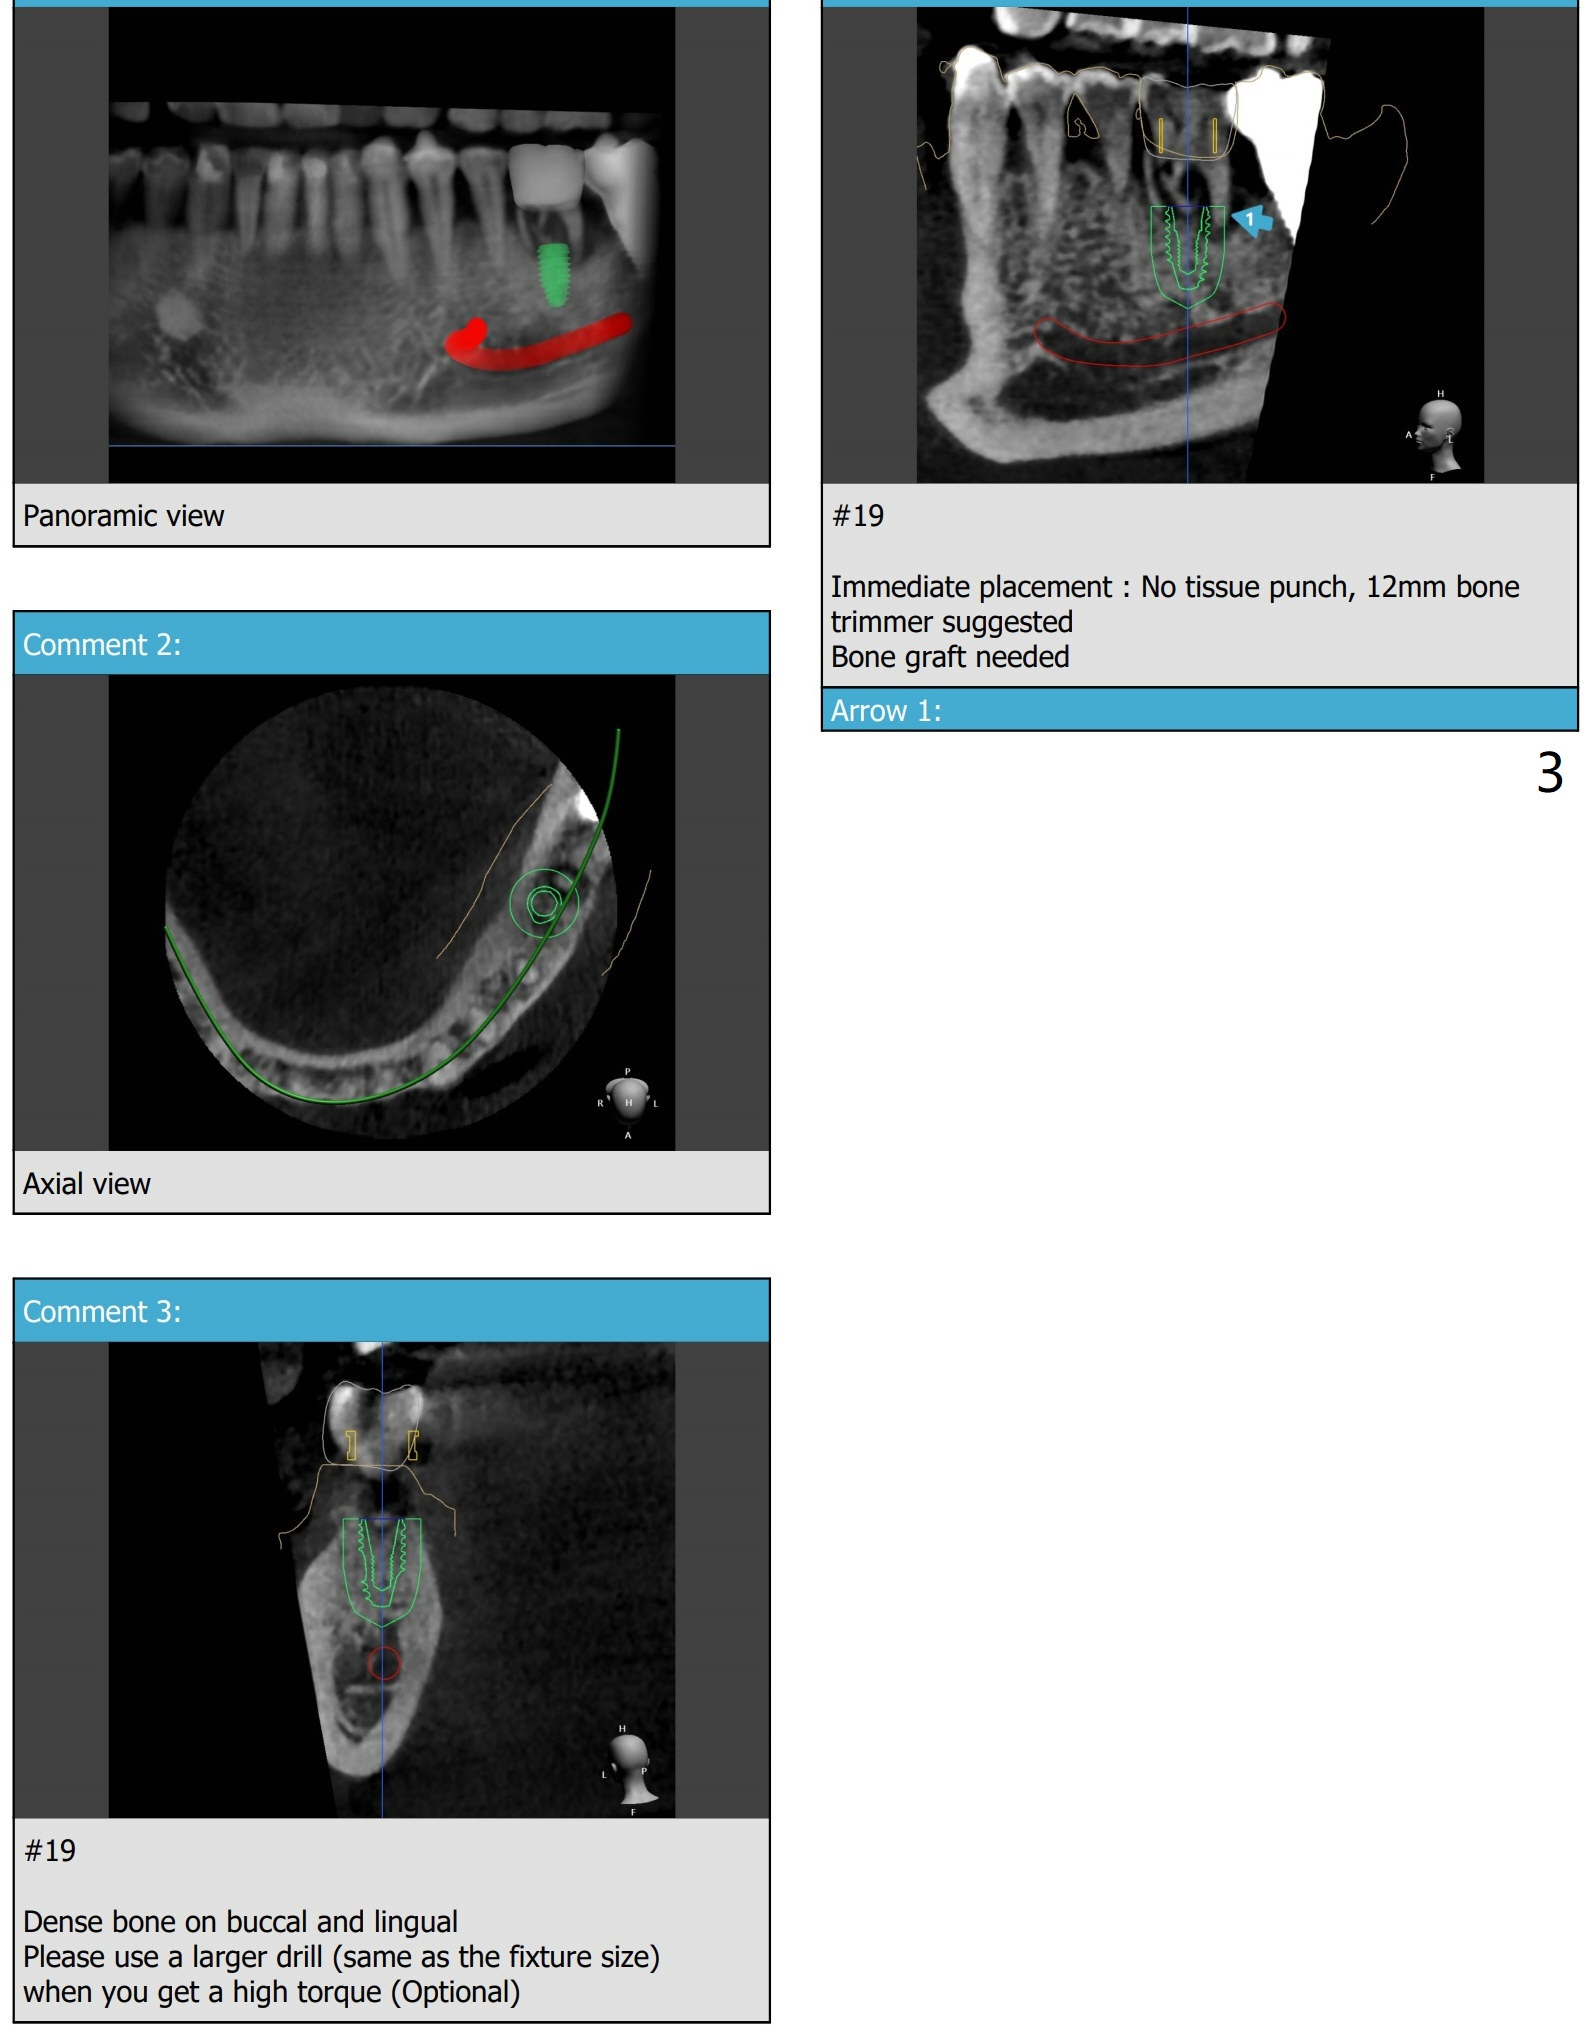

A 59-year-old man has toothache associated with root split of the tooth #19. Due to severe bone loss, a 4.5x8.5 mm implant will be placed in the septum. PRFx1. Remove guide after 3.5x7.3 mm drill or place a 4x10 mm implant to determine whether there is bone buccolingually to hold the 4.5x8.5 mm fixture.